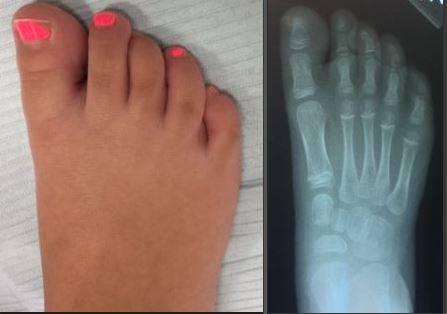

Query: Painful Toe Contractures in 4 Year Old Female

This is a 4 year old female patient with painful third toes both barefoot and with shoes. The third toe underlaps the second toe. Her toes are flexible and reducible. Treatment has consisted of taping and stretching, without any improvement.

Painful Toe Contractures in 4 Year Old Female |

What is the underlying cause? Will the patient "grow out" of this? Will custom orthotics help? Are there any other conservative treatment options?